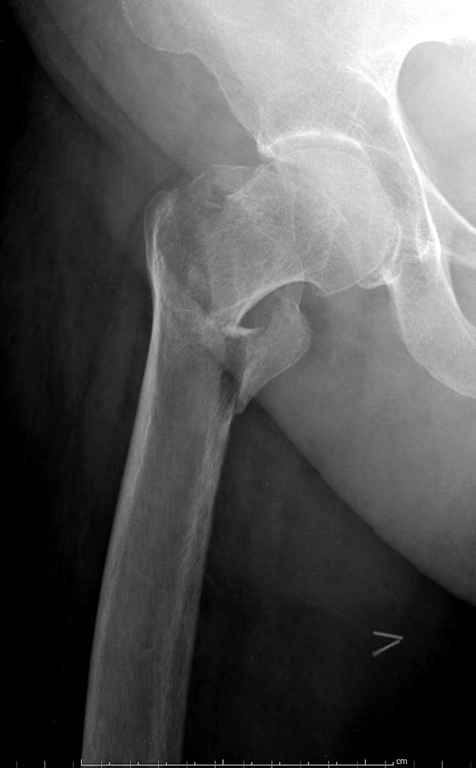

В данном случае в головке бедра и в вертлужной впадине огромный дефект, навряд ли удалением импланта или заменой на другой можно сохранить сустав.

Вашему вниманию представляется похожий случай, пациентке 70, осложнился в течение одного месяца после операции. Ревизия с заменой сустава, кабельная фиксация на трохантер. При установке в дистальном диафизе обнаружен тонкий кортикальный слой и сделана профилактика от возможного перелома аллографтом.